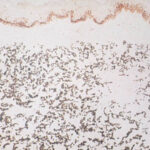

Histopathology. Histologic examination of the involved skin reveals considerable accumulations of swollen and irregularly clumped fibers staining like elastic fibers in the middle and lower thirds of the dermis; that is, they stain deeply black with orcein or Verhoetrs stain . Although normally elastic fibers do not stain with routine stains such as hematoxylin-eosin, the altered elastic fibers in pseudoxanthoma elasticum stain faintly basophilic because of their calcium imbibition. Staining for calcium with the von Kossa method also shows these fibers well. |

In the vicinity of the altered elastic fibers, there may be accumulations of a slightly basophilic mucoid material, which stains strongly positive with the colloidal iron reaction or with Alcian blue . The number of collagen bundles is reduced in such areas, and numerous reticulum fibers are seen on impregnation with silver . In some cases with pronounced elastic tissue calcification, a macrophage and giant cell reaction may be present . |

Histogenesis. Electron microscopic examination shows that the calcification occurs in normal-appearing elastic fibers . In some patients, especially in young persons, only some of the elastic fibers in the lower dermis are calcified, and the calcification is variable in degree. However, in adult patients, most elastic fibers show considerable calcification and, as a result, degeneration. Early calcification of elastic fibers consists either of diffuse granular deposits throughout the elastic fiber or of dense aggregates that may be located in the center or near the margin of the fiber (EM 5). With progression of the calcification, the elastic fibers ultimately become fully calcified, showing marked swelling and bizarre distortions. In addition, heavy calcium deposits may be seen in the ground substance adjacent to elastic fibers and free in the ground substance. The presence of calcified material outside of elastic fibers can be explained by the disintegration of completely calcified elastic fibers . |